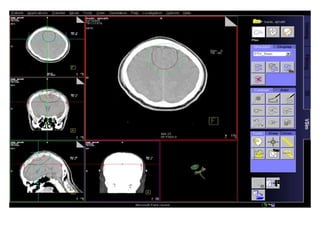

Robotic Radiosurgery

Highly precise RT delivery system

- Respiratory tracking

- Fiducial based tracking system

- Intra-fraction motion correction

- Uncomparable dose distribution

- X-ray based image verification

Hypofractionated RT

- High dose short course RT

- Higher BED delivered to target